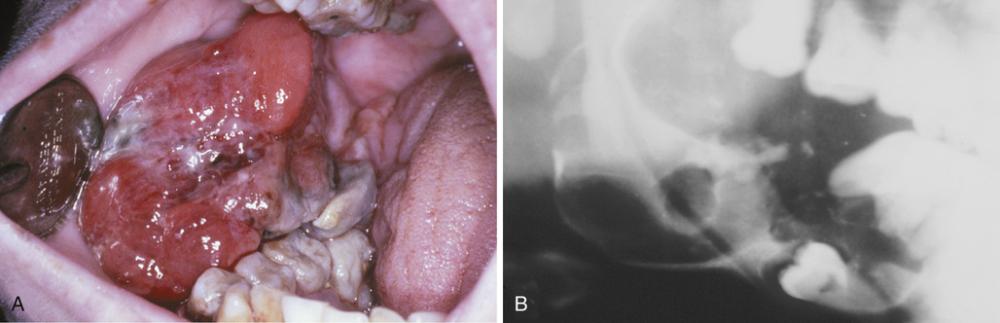

calcifying odontogenic cyst

A well-circumscribed mixed radiolucent/radiopaque lesion in the right body of the mandible. Note root resorption of adjacent teeth.

- Expansion of the posterior maxillary alveolus caused by a large pink lesion.

- Panoramic radiograph showing a large radiolucency with a small calcified structure is seen in the lower portion.